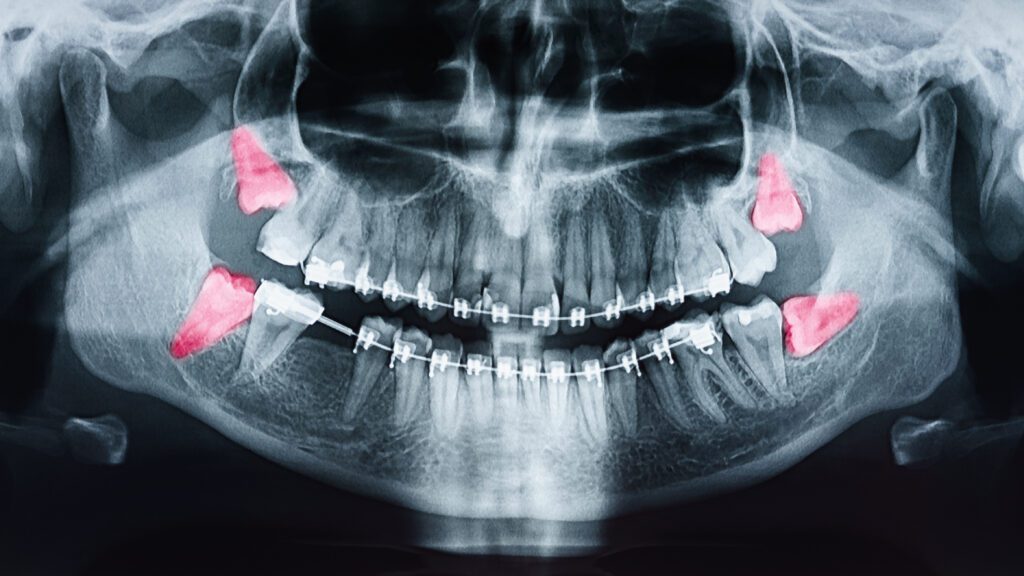

Our oral surgeons at Cameo Dental Specialists have extensive training and experience in performing wisdom teeth removal. We use advanced imaging technology to plan your procedure with precision, and we offer sedation options to keep you comfortable throughout.